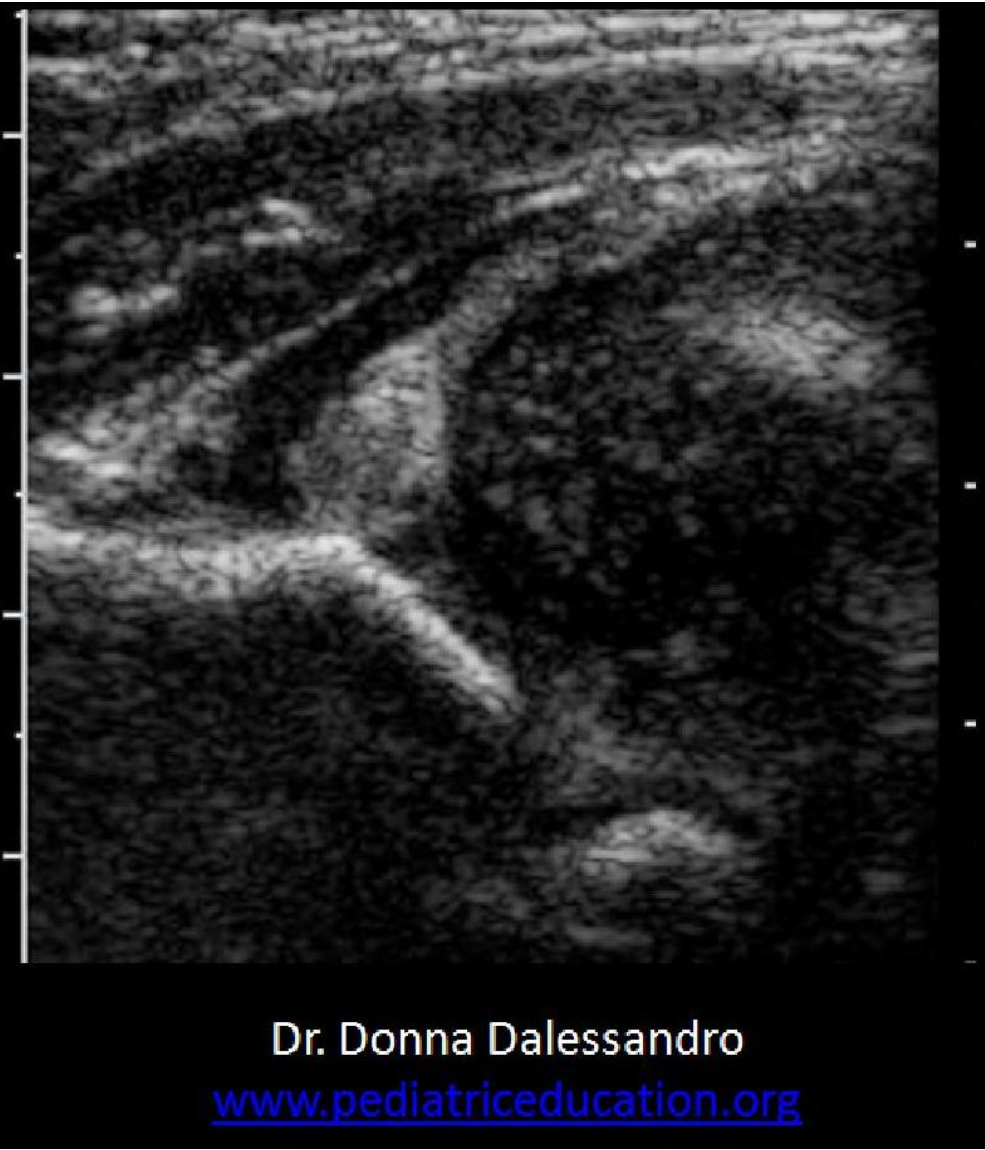

A 3yr old is scanned due to vomiting and a palpable lump in the abdomen.

These findings are most suggestive of:

A. Pyloric stenosis

B. Biliary ascaris

C. Intussusception

D. Appendicitis

The image demonstrates intussusception with the the inversion of one portion of the intestine within another. Note the body marker indicates the area of interest is on in the mid to lower quadrant on the left side. The aorta is also visualized on the image. Pyloric stenosis is diagnosed in early infancy and would be located in the epigastric/RUQ area. The aorta would not be demonstrated in the area of the appendix.